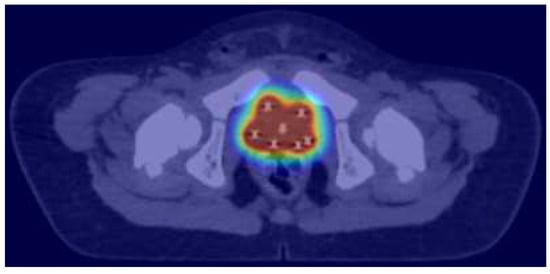

3.4. Bladder/Prostate/Female Genito-Urinary Organs